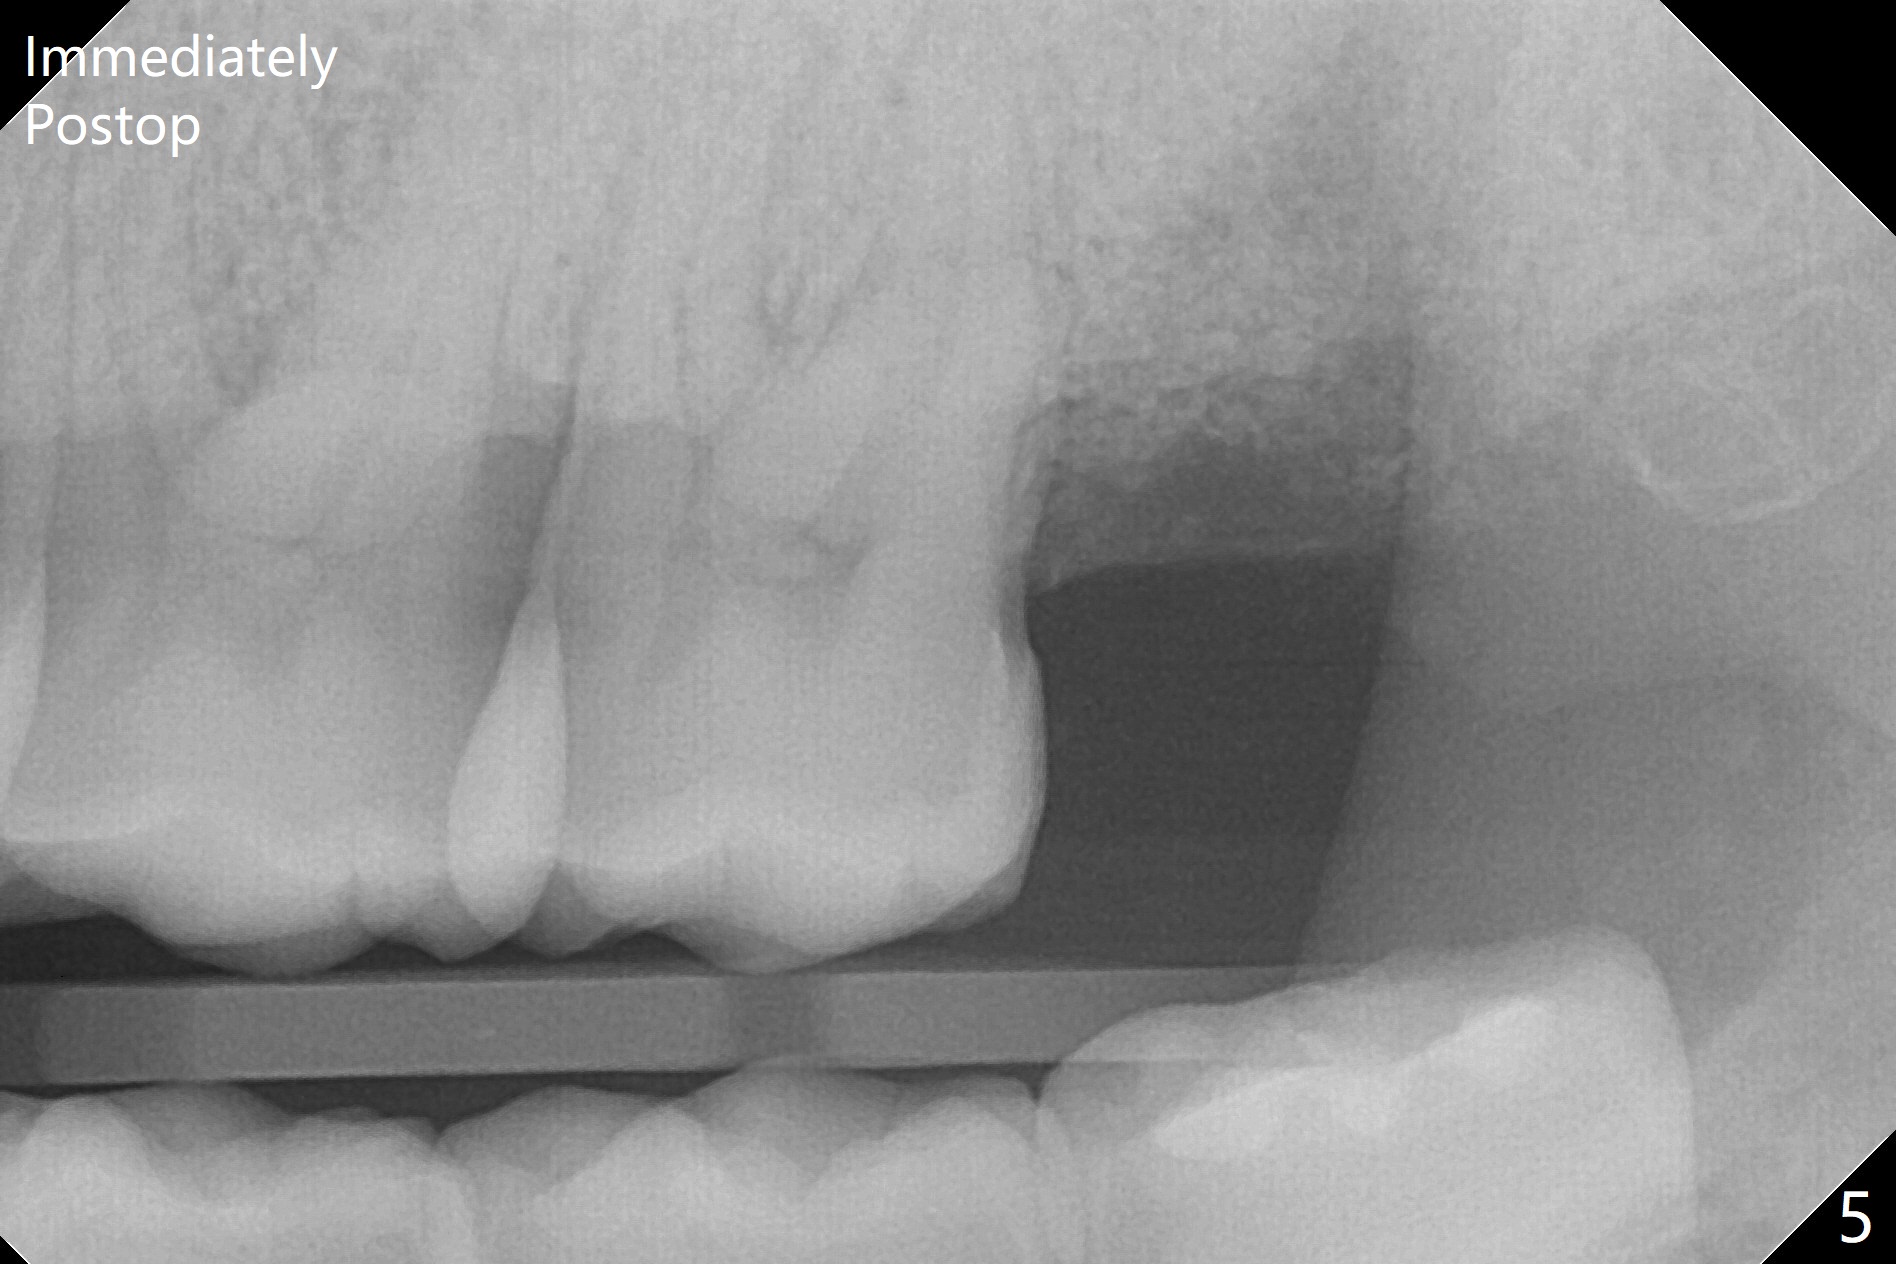

A 35-year-old woman requests extraction of the tooth #1 (food impaction between #1 and 2, Fig.1) and 16 (pain and 6 mm pockets between #15 and 16, Fig.2). In spite of the fact that there is bone loss between #14 and 15 (Fig.3), there is no deep pocket between them. After extraction of #16, SRP is performed in the distal surface of #15 with removal of granulation tissue and application of Endogain. Osteogen plug (Fig.4 O) is placed in the apical and distal portion of the socket of #16 (red dashed line), while allograft (G) against the distal root surface of #15. Finally Collagen plug (C) and 6-month membrane are placed in the opening of the socket, followed by suturing and periodontal dressing. The bone density is high post #1 extraction (Fig.6), related to difficult removal. It appears that bone graft at #16 (^) remains in place 15 months postop. Since no buccal trough is made for extraction, the external oblique ridge is present at #17 and 32 before and after surgery. Bond Apatite is placed with Collagen Plug (Fig.7).